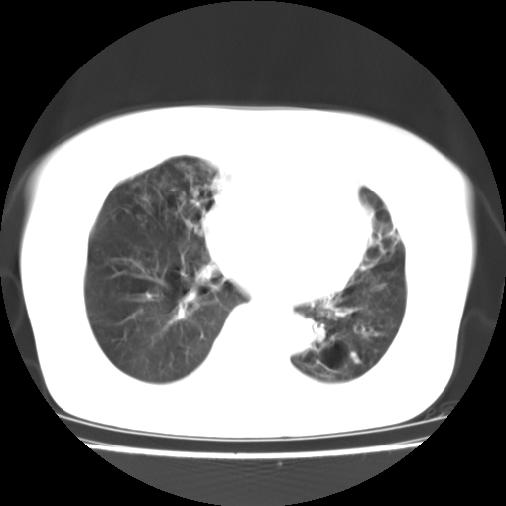

标题: CT16957:F56Y,这是先天性肺囊肿,还是支气管扩张??? [打印本页]

标题: CT16957:F56Y,这是先天性肺囊肿,还是支气管扩张???

女性病人,56岁,反复咳喘30余年,伴大量脓痰,偶有痰中带血。

此病例在科室里有较大的争议,我认为是先天性肺囊肿(理由是:两者起病年龄都较轻,都有咯血及脓痰的症状,而先天性肺囊肿壁薄;而支扩的囊腔旁一般都能看到伴行的血管影,形成“印戒”征)。以上为个人的意见,请高手们指点一下。

本例应为支气管扩张并感染,与囊肿区别在于其大小,分布,壁改变,与肺动脉关系,形态等来鉴别,要点大家都说得差不多了,囊肿要大些,分散些,靠外围一些,而支扩靠内一些,聚拢些,小一些且易聚拢呈葡萄状,不能单从囊壁厚度来评价,特别是有粘液栓类的改变更加支持支扩,有时支扩亦与囊肿混在一起并存.个人意见仅供参考.